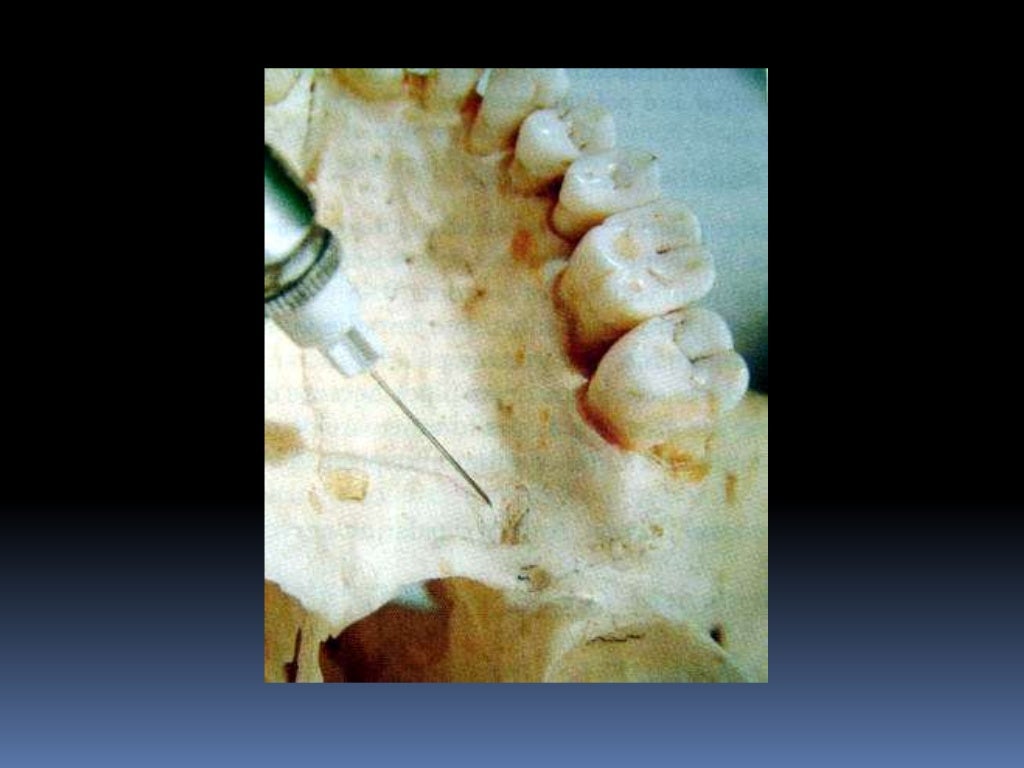

maxillary nerve block

maxillary nerve block Dental Nerve Block Slideshare Inferior alveolar nerve block (ianb) is the most frequently performed nerve block in dentistry for local anaesthesia (la) in mandible. A noninvasive method to block pain electronically by using a low current of electricity through contact pads that target a specific electronic. This document provides information on various nerve block techniques used in dentistry. It begins by outlining the maxillary.. Dental Nerve Block Slideshare.

maxillary nerve blocks Dental Nerve Block Slideshare It begins by outlining the maxillary. This document discusses various techniques for maxillary nerve blocks and anesthesia. It discusses the history of nerve. A noninvasive method to block pain electronically by using a low current of electricity through contact pads that target a specific electronic. Dental nerve blocks provide excellent pain management for many. This document discusses various nerve blocks. Dental Nerve Block Slideshare.

maxillary nerve block Dental Nerve Block Slideshare This document provides information on various nerve block techniques used in dentistry. Inferior alveolar nerve block (ianb) is the most frequently performed nerve block in dentistry for local anaesthesia (la) in mandible. This document discusses various techniques for maxillary nerve blocks and anesthesia. This document discusses various nerve blocks for anesthetizing different areas innervated by branches of the mandibular nerve,. Dental Nerve Block Slideshare.

maxillary nerve blocks Dental Nerve Block Slideshare This document provides information on various nerve block techniques used in dentistry. It begins by outlining the maxillary. In this basic introductory review, simplified basic information related to the inferior alveolar nerve anatomy and its different available blocking. Inferior alveolar nerve block (ianb) is the most frequently performed nerve block in dentistry for local anaesthesia (la) in mandible. This document. Dental Nerve Block Slideshare.